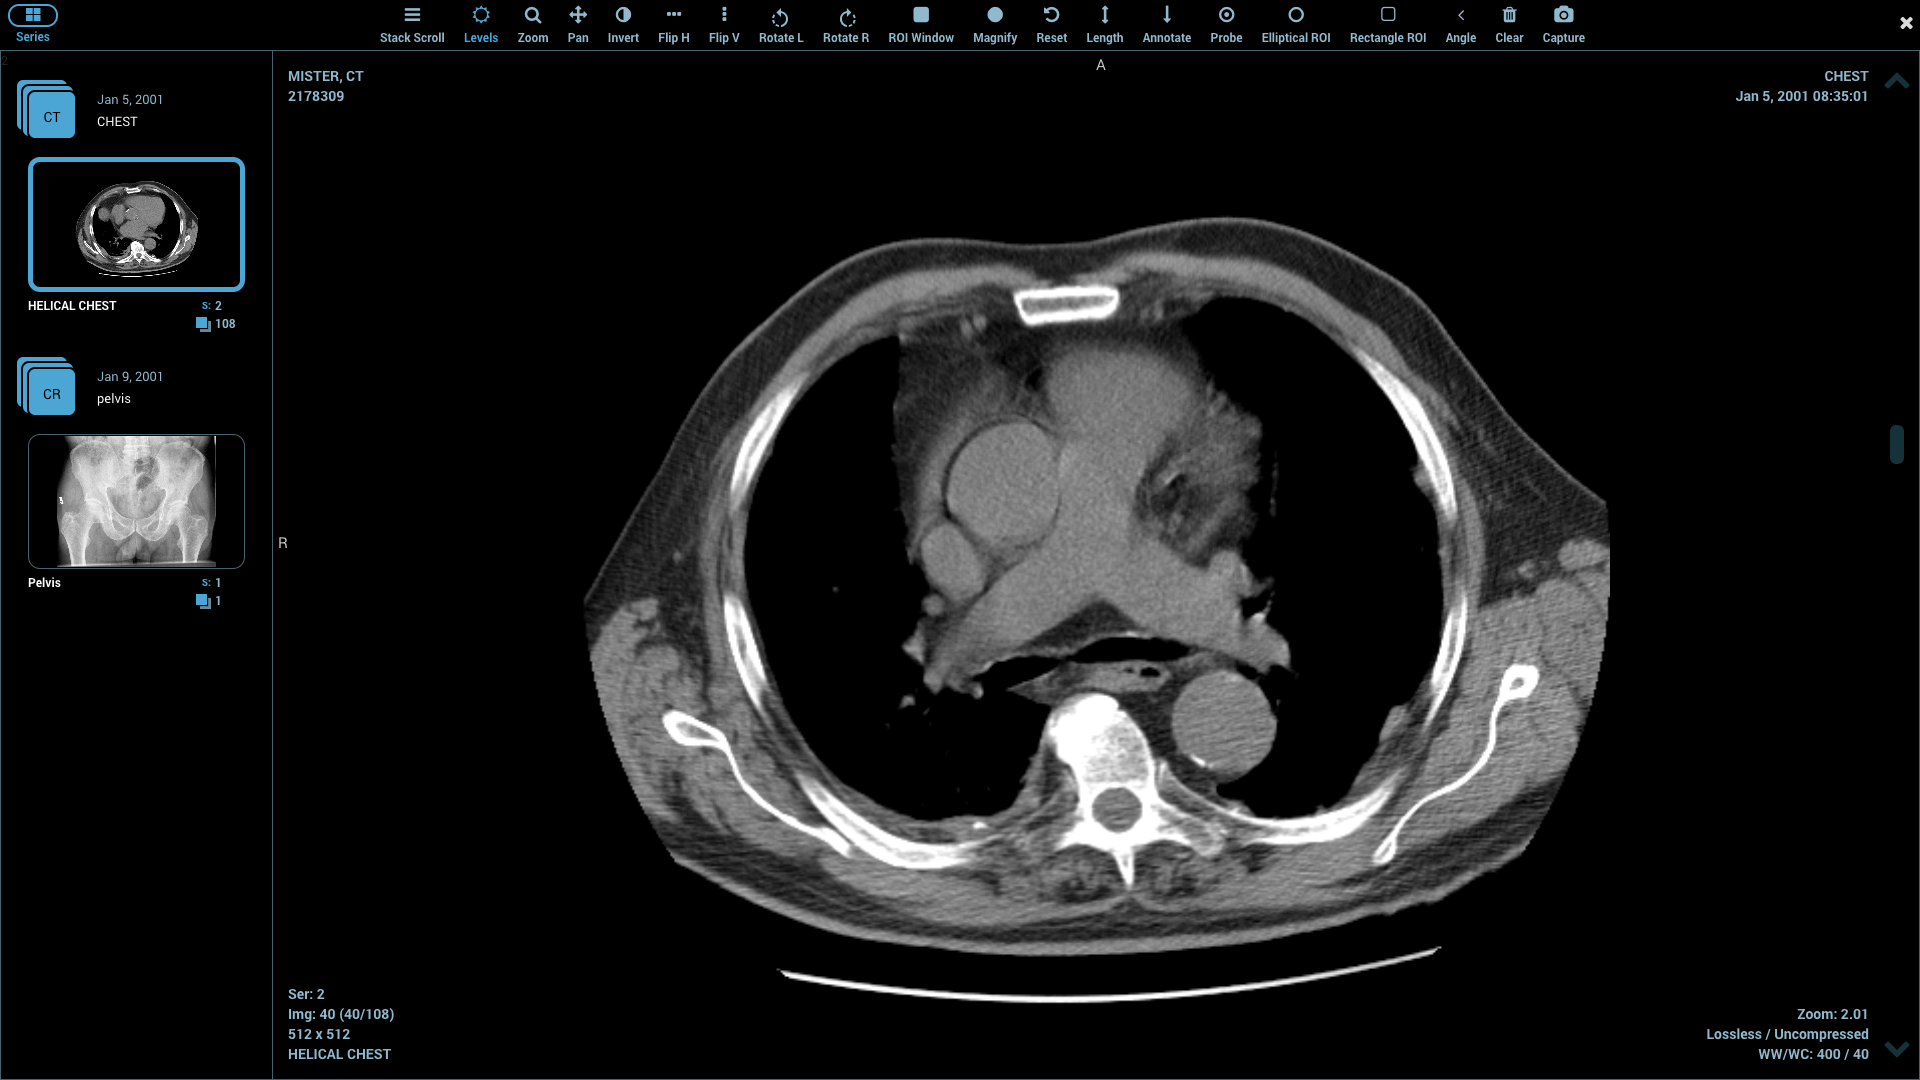

PostDICOM is one of the best DICOM viewers that offers almost all of the above features. It is compatible with Windows, Mac OS X, and Linux. It can be operated from android devices and iOS-based systems. PostDICOM comes with a cloud-based PACS, which allows you to access data from any device, anywhere, at any time. The viewer allows advanced image manipulation, such as 3D reconstruction, 3D volume rendering and MIP, and image fusion. It also offers an interface for creating reports, sharing files, and immediate uploading of all patient data to the cloud PACS.

The cloud-based PACS is unique to this software and offers several advantages. It allows researchers to upload relevant images on the PACS server for viewing, processing, and analyzing at various stages during the course of their clinical research. This ensures complete data integration and a smooth workflow.

Although paid subscriptions are available, the free trial version itself has several premium features. The cloud PACS offers free trial to its paid subscriptions, shares a month, and one or more user logins. These can be increased with different paid subscriptions. PostDICOM offers technical support for the free.

| 1. | PostDICOM | Windows, Mac OS X, Linux, Android, iPhones and iPads | Free trial, view the uploaded images after trial, cloud-based PACS | Y | Y | Y | Picture files, documents | N.A. | Intel Core i3/ 2 GB RAM | Free trial. Paid version has more cloud storage, Medical Device Communicator and longer share duration |